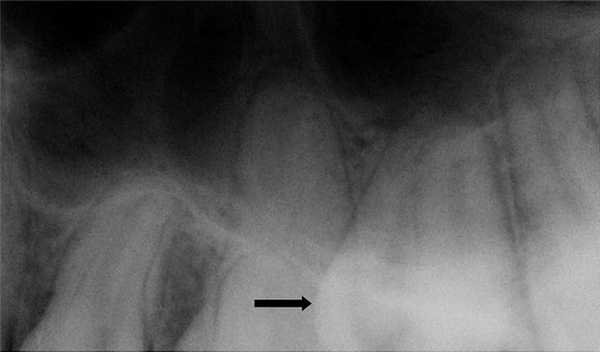

Сверхкомплектный зуб определен как парамоляр. Коронка парамоляра имела два бугорка и весьма сильно напоминала строение постоянного премоляра. Зуб повернут по оси, с расположением щечной поверхности дистально и мезиальной поверхности щечно. На мезиальной стороне парамоляра обнаружено кариозное поражение (Фото 2). Осмотр мягких тканей выявил воспаление пародонта между первым и вторым молярами и парамоляром. Сделаны рентгеновские снимки: панорамный, прицельный и окклюзионный. Чтение панорамного снимка было затруднено из-за небного расположения зуба. На прицельном и окклюзионных снимках обнаружено, что сверхкомплектный зуб поражен кариесом и имеет один корень (Фото 3 и 4).

Фото 3: Прицельный рентгеновский снимок, показывающий парамоляр с полностью сформованным зубом (указан стрелкой).

Фото 4: Окклюзионная рентгенограмма верхней челюсти, показывающая сверхкомплектный зуб (стрелка).